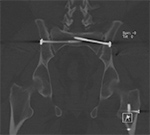

Periprosthetic 3D Reconstruction. (A) 3D reconstruction of osseous anatomy surrounding right total shoulder arthroplasty without dual-energy technique demonstrates significant artifact limiting evaluation of hardware and glenohumeral joint. (B) Dual-energy CT 3D reconstruction focused on metallic hardware demonstrates excellent visualization of hardware with metaglene screw fracture (arrow). Dual Energy CT. (A) Axial CT image acquired with dual energy technique demonstrates minimal artifact secondary to sacroiliac joint screws. (B) Coronal multi-planar reformation demonstrates excellent visualization of the osseous anatomy and hardware with further minimization of artifact.